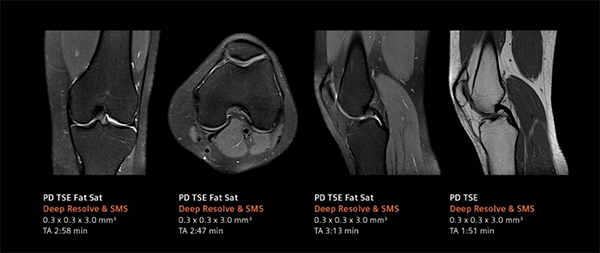

デジタル化により高画質と撮像時間の短縮を実現するべく,画像再構成にAI技術を用いて開発されたのがDeep Resolve(ディープ・レゾルブ)。

Deep Resolveは,ディープラーニング(深層学習)とターゲットデノイジング(ノイズの標的除去)により画像のノイズ除去や撮像した画像を高分解能化することで,高品質な画像の取得と撮影時間の短縮※を可能にする。検査精度やワークフローの向上のほか,被検者の快適性や質の高い医療へのアクセス向上が期待される。

左:ルーチン検査画像,右:Deep Resolveによる再構成画像

整形領域のルーチン検査画像(合計検査時間:10:49 min)